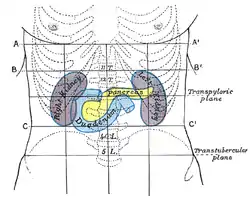

One method by which the location of the abdominal contents can be appreciated is to draw three horizontal and two vertical lines.

Horizontal lines

- The highest of the former is the transpyloric line of C. Addison, which is situated halfway between the suprasternal notch and the top of the pubic symphysis, and often cuts the pyloric opening of the stomach an inch to the right of the mid-line. The hilum of each kidney is a little below it, while its left end approximately touches the lower limit of the spleen. It corresponds to the first lumbar vertebra behind.

- The second line is the subcostal line, drawn from the lowest point of the subcostal arch (tenth rib). It corresponds to the upper part of the third lumbar vertebra, and it is an inch or so above the umbilicus. It indicates roughly the transverse colon, the lower ends of the kidneys, and the upper limit of the transverse (3rd) part of the duodenum.

- The third line is called the intertubercular line, and runs across between the two rough tubercles, which can be felt on the outer lip of the crest of the ilium about two and a half inches (64 mm) from the anterior superior spine. This line corresponds to the body of the fifth lumbar vertebra, and passes through or just above the ileo-caecal valve, where the small intestine joins the large intestine.

Vertical lines

The two vertical or mid-Poupart lines are drawn from the point midway between the anterior superior spine and the pubic symphysis on each side, vertically upward to the costal margin.

- The right one is the most valuable, as the ileo-caecal valve is situated where it cuts the intertubercular line. The orifice of the appendix lies an inch lower, at McBurney's point. In its upper part, the vertical line meets the transpyloric line at the lower margin of the ribs, usually the ninth, and here the gallbladder is situated.

- The left mid-Poupart line corresponds in its upper three-quarters to the inner edge of the descending colon.

The right subcostal margin corresponds to the lower limit of the liver, while the right nipple is about half an inch above its upper limit.